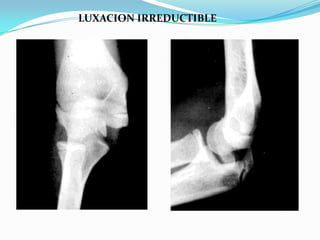

Luxación Irreductible:

1.-interposición de cápsula articular.

2.- Interposición de Fracturas(Ej. Epitróclea )

3.- Interposición del bíceps braquial.

4.- Interposición de ligamento anular.

LUXACION IRREDUCTIBLE